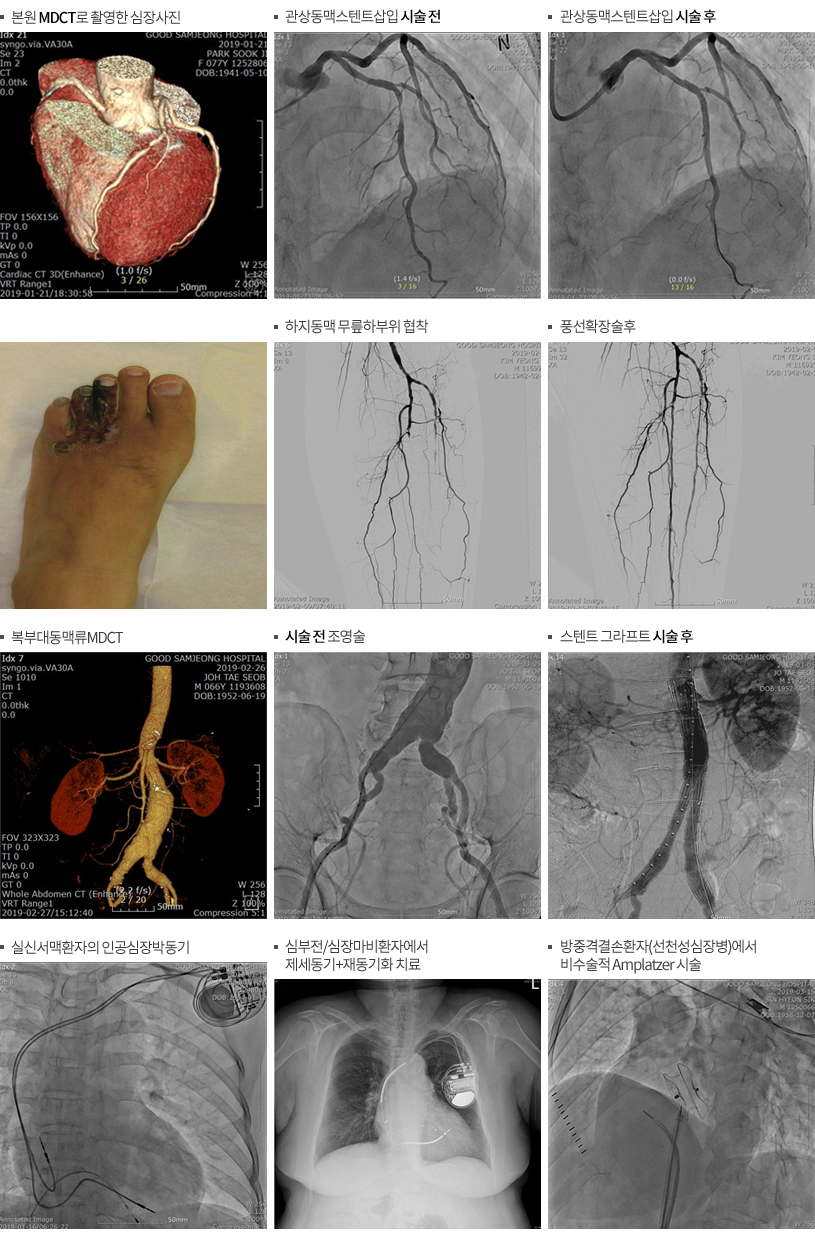

본원에서는 우수한 의료진과 최신 심혈관 검사 및 치료 장비를 도입하여 24시간 심혈관 질환을 진료할 수 있는 심혈관 센터를 2018년 11월 1일 개설하여 심장 및 심장을 둘러싼 관상동맥 질환과 대동맥, 상하지 동맥, 하지 심부정맥, 경동맥 질환에 대한 정확한 진단 및 중재적 시술을 할 수 있는 시스템을 갖추었습니다.

또한 365일 24시간 심장내과 전문의의 진료와 응급진료체계 구축으로 지역 내 주민들의 건강 지킴이로서 역할에 최선을 다할 것입니다.